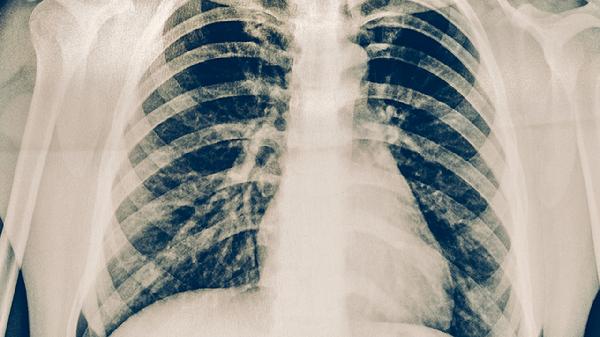

持续咳嗽咳痰超过2周、低热盗汗或痰中带血时,应立即进行痰涂片检查和胸部影像学检查。确诊患者需严格完成6-8个月规范治疗,利福平片、异烟肼片、吡嗪酰胺片等抗结核药物需联合足量使用。密切接触者应接受结核菌素试验筛查。

预防肺结核需建立健康生活方式,保证每日7-8小时睡眠,戒烟限酒减少呼吸道刺激。高危职业人群应每年进行胸部X线检查,学校等集体单位需落实晨检制度。出现可疑症状时避免讳疾忌医,早发现早治疗可完全治愈并阻断传播链。日常注意保暖防感冒,呼吸道感染期间尽量减少到人群密集场所活动。